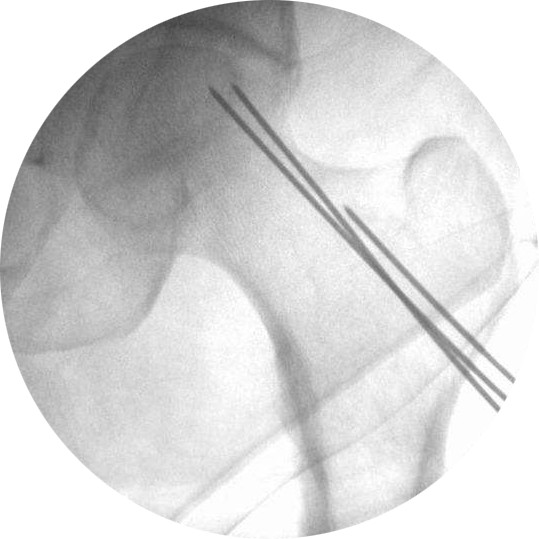

微创钻孔减压术:目前公认的有可能有效的手术方案。无需切开,用直径2mm左右的钢针透皮向股骨头钻几个孔。手术创伤很小,疼痛很轻。现在还有钻孔后复合干细胞植入。